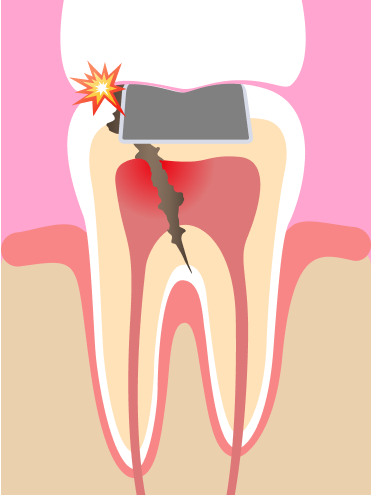

杜牙根後牙齒的剩餘結構較少,牙齒變得脆弱容易斷裂。

牙冠可以提供額外的保護,防止牙齒崩裂。